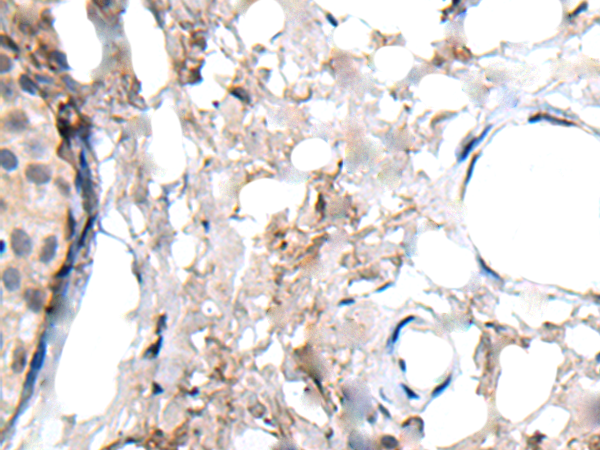

IHC positive control:

Human liver cancer and human lung cancer